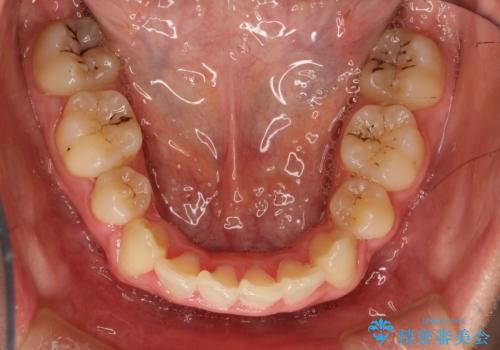

患者様が装置を早期に除去したいという希望もあり、少々下の前歯のがたつきが残った状態で矯正を終了しました。

全体的ながたつきがなくなり、見た目の印象がよくなりました。